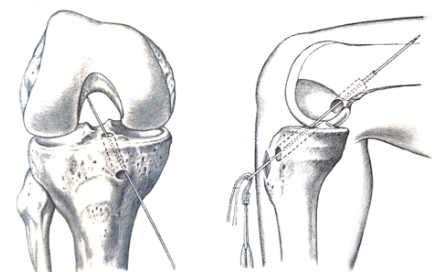

前十字靭帯は膝の関節の中のすねの骨の前から太ももの骨の後ろへと走る靭帯で、方向を換える、急にストップする際に緊張し動きを制御します。損傷の原因としてはバスケットボール、サッカーでのカット動作、バレーボールの着地、スキーのターンの際 などで自分の力で損傷する場合(非接触型損傷)と、柔道、ラグビーなど、他者と接触して 受傷する場合(接触型損傷)があります。前十字靭帯が損傷するとカット動作、ジャン プの着地などで膝の不安定感が出現し、膝がずれる(膝くずれ)症状が出現します。膝くずれ を繰り返すと関節内の半月が損傷され、半月板 症状(膝のひっかかり、ロッキング)が生じて きます。膝くずれが頻繁に生じるとその際に、関節内の半月板、軟骨が損傷され、早期に変形性関節症になってしまいます。また前十字靭帯は損傷されると関節内で経時的に吸収 されてしまいますので、切れた靭帯をつなげた だけでは元に戻らず、靭帯の代わりとなるもの を作り直す(再建術)必要があります。今後、 スポーツ活動をする方や日常生活でも不安定感 が残る方は手術を受ける必要があります。手術方法としては大腿骨(太ももの骨)、脛骨(すねの骨)に骨 孔(骨のトンネル)を掘り移植する腱を通し、 失った前十字靭帯の機能を再建する手術です。 膝蓋骨(お皿)の内外側にそれぞれ7mm程度の、 すねの内側に3cm程度の傷ができます。移植 腱を採取し、多重折りに束ねます。大腿骨、脛骨に骨孔を作製、移植腱を通し、大腿 骨側は金属製のボタンで、脛骨側はステープルで 固定します。移植腱としてはハムストリン グ腱(半腱様筋腱、薄筋腱)、骨付き膝蓋腱など が使用されます。移植した腱と骨が一体化するのに9ヶ月程度かかるため、時期に応じてやるべきことと、すべ きではないリハビリがあります。 術直後から膝の曲げ伸ばし、太ももの前の筋力 強化を開始します。徐々に歩行を許可しますが、 手術した膝を守るため術後1ヶ月程度は松葉杖を 使用していただきます。術後1ヶ月程度からスク ワットを開始し、筋力の回復をみながら術後3ヶ月からジョギング、術後5ヶ月頃から徐々にス ポーツ種目別の練習に参加し、術後9ヶ月に完全 復帰を目指します。